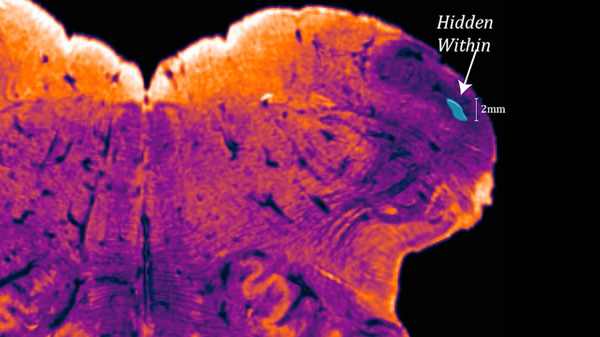

پروفیسرجارج پیکسی نوس نے ایک عشرے سے زائد عرصے تک تحقیق اورلٹریچرکے مطالعے کے بعد کہا ہے کہ انسانی حرام مغز(اسپائنل کورڈ) اور دماغ کے درمیان اینڈوریسٹائی فورم نیوکلیئس موجود ہے جو انسان کو دیگرجانداروں سے ممتاز کرتا ہے۔ یہ عضو 'انفریریئر سیربرل پیڈنکل' سے جڑا ہوتا ہے جس پر اب تک کسی ماہر کی نظر نہیں گئی تھی۔

اگرچہ اینڈوریسٹائی فورم نیوکلیئس کا درست کردار اب تک پوشیدہ ہے لیکن یہ جس مقام پر واقع ہے وہاں دماغ اور حرام مغز ملتے ہیں۔ یہ حصہ انسان کے ہاتھ پیروں کی حساس ترین حرکات وسکنات یعنی سوئی میں دھاگہ ڈالنے سے لے کر متوازن ہونے، بیٹھنے کے انداز اور جسمانی چلت پھرت کو کنٹرول کرتا ہے۔